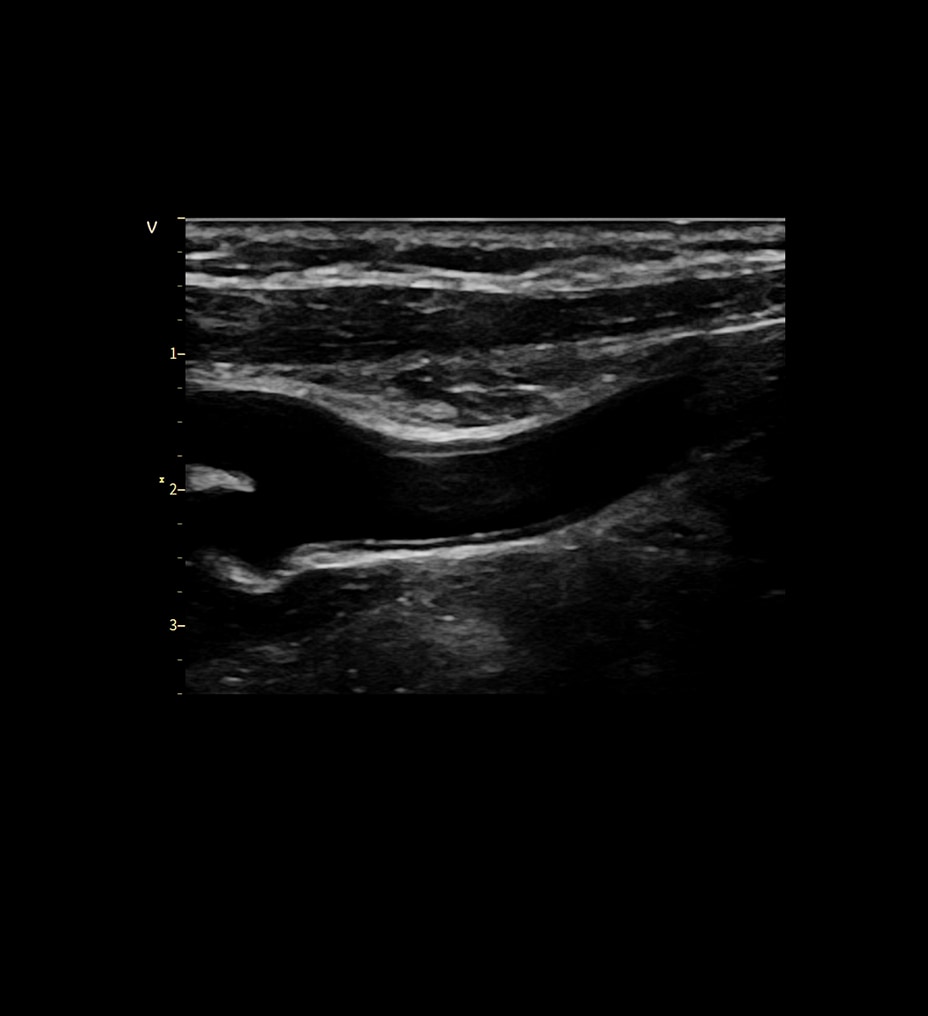

Alimentado por la tecnología SignalMax™, para que no tenga que comprometer la calidad de la imagen para la portabilidad